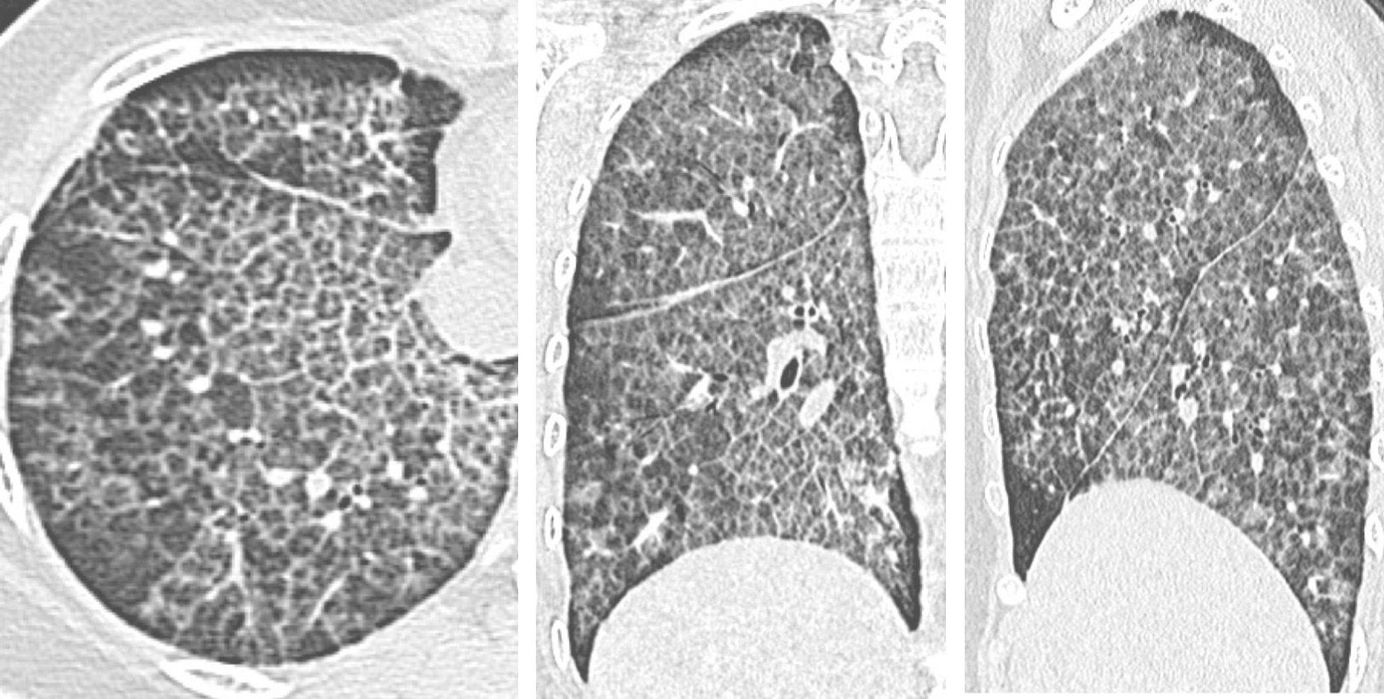

Case 26 - 16-Years Old with Progressive Breathlessness Members Public

16-years old girl with subacute onset progressive breathlessness and a crazy-paving pattern on CT. Free to view till 13th September, but you need to subscribe with your email ID.